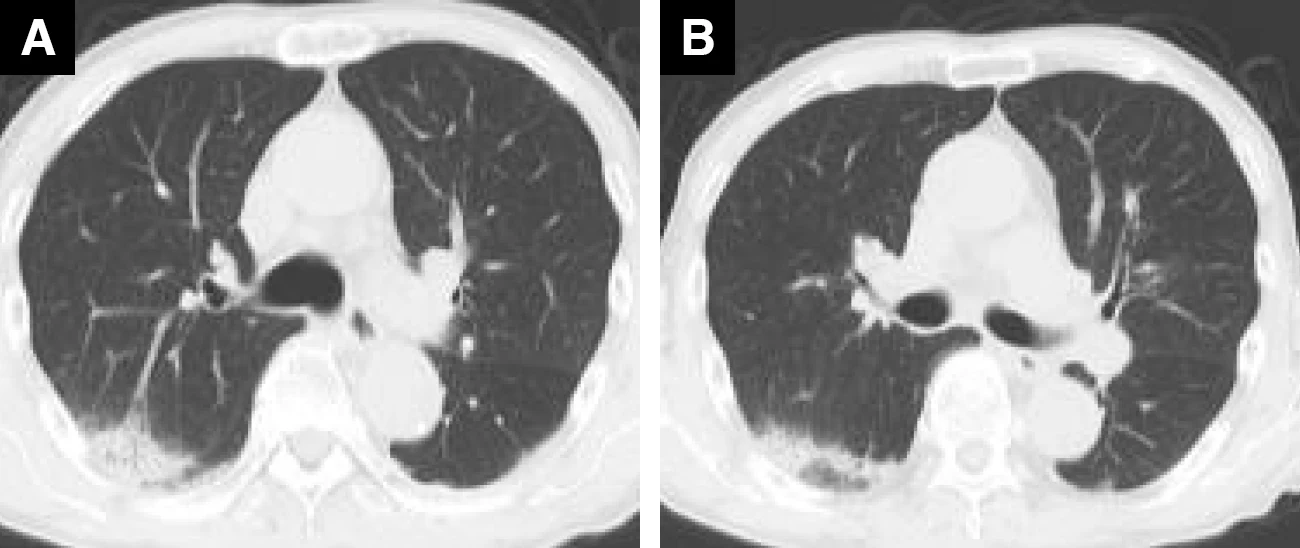

ドセタキセル投与症例(63歳、男性、乳がん)

A : 薬剤投与前 B : 薬剤投与後(紹介時)

Bでは広範囲のすりガラス影がみられ、HP(過敏性肺炎)パターンと考えられた